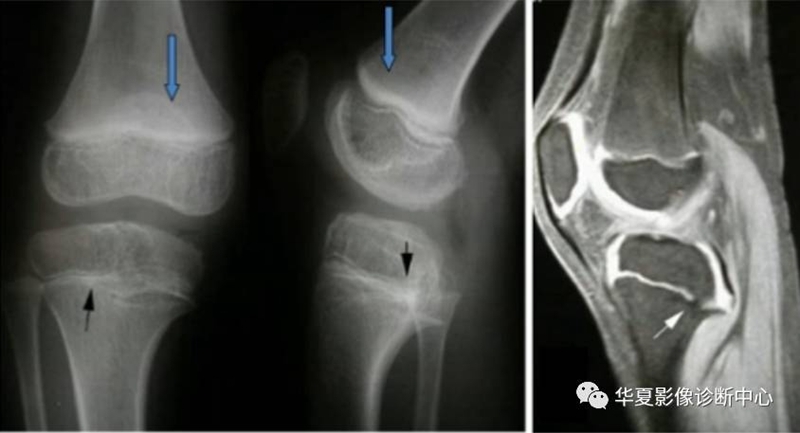

侵犯关节软骨:关节面模糊,中断消失。关节间隙狭窄,宽窄不一,并见肿瘤影。

侵犯骺板软骨:先期钙化带境界模糊,密度不均,中断消失,骺板软骨出现软组织影。

股骨远端正常骨骺,侵犯骺板软骨:出现软组织且宽窄不一